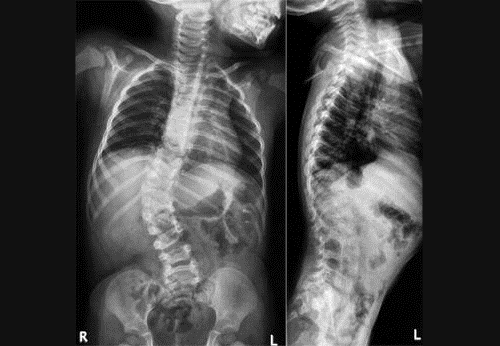

Сколиоз третьей степени характеризуется углом искривления от 26 до 50º и выраженной торсией (поворотом) позвонков. Искривление может происходить как влево, так и вправо. Выделяют следующие типы деформации:

Диагностика сколиоза не представляет особых трудностей. Врач должен исключить функциональные расстройства, патологические кифозы и лордозы, а также заболевания, такие как болезнь Бехтерева и болезнь Шейермана-Мау. Основным методом диагностики сколиоза 3 степени является рентгенография. При первом исследовании допускается выполнение снимка в стоячем положении. Повторная рентгенография проводится как в вертикальной, так и в горизонтальной позе пациента.

Ключевым признаком сколиоза является отклонение позвоночника от вертикальной оси. При анализе рентгеновских снимков внимание уделяется:

- расположению скошенных, базальных, промежуточных и кульминационных позвонков;

- наличию остеохондроза или артроза;

- локализации сколиотической дуги.

Степень искривления определяется врачом на основе снимка с использованием методики Кобба. Для этого на рентгенограмму наносятся две линии, параллельные замыкательным пластинкам позвонков, не вовлеченных в искривление. В дополнение к рентгенографии может проводиться магнитно-резонансная томография. Важную роль играют также результаты опроса и осмотра. При сборе анамнеза врач выявляет возможные факторы риска деформации позвоночника, такие как травмы или неправильный образ жизни.